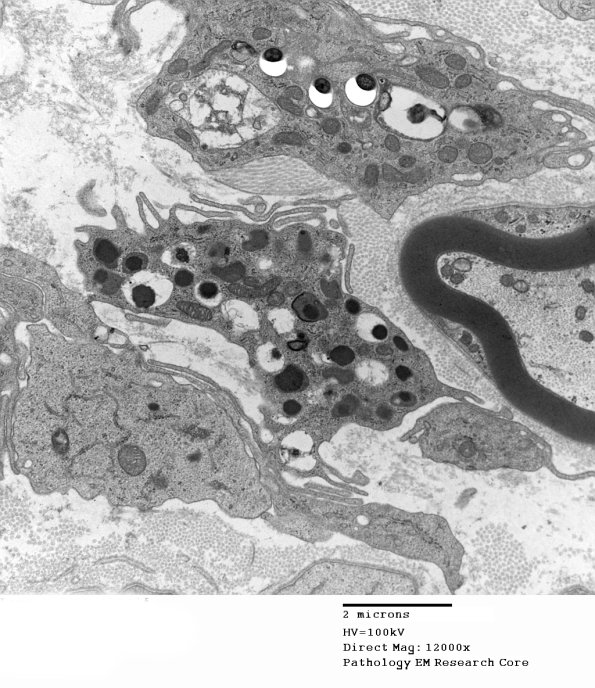

Several images showing numerous bacteria within macrophages and others in Schwann cells. (electron micrographs)